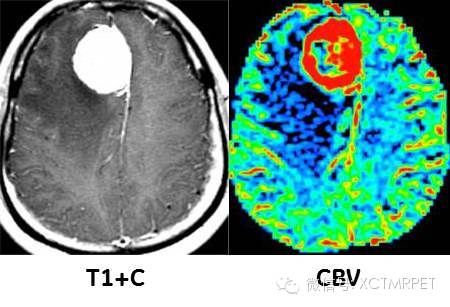

脑膜瘤血供判断: T1增强图像上可见明显强化的占位肿块,周围伴低信号水肿带,PWI的CBV图像上,肿瘤血供异常丰富。